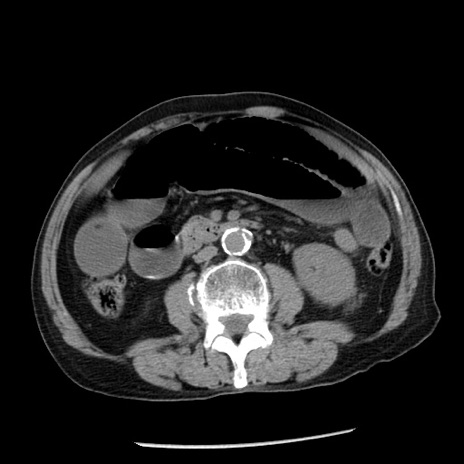

症例26(横断像)

【症例】80歳代男性

【主訴】嘔吐

【現病歴】昨晩2回嘔吐あり、今朝になっても嘔吐あり。来院。

【既往歴】胃潰瘍

【身体所見】意識清明、BT 37.6℃、BP 166/95mmHg、HR 100bpm、SpO2 97%、腹部:平坦・軟、腸蠕動音聴取良好、圧痛なし。

【データ】WBC 21900、CRP 1.46